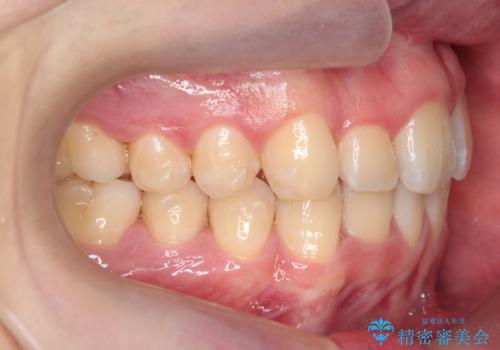

前歯のすき間、犬歯の異所萌出 乳歯を抜かずに矯正

- 前歯のすきまと八重歯を主訴に来院。

左上の乳犬歯が残っており、その下から生えてくるはずの犬歯(永久歯)が左上小臼歯部に萌出していました。

左上の乳犬歯は根もしっかりしていたため、

を提案し、➀を選択されました。

将来的にインプラントは希望されないとのことだったため、乳歯の部分は隙間を開けてインプラントを入れる用のすき間を確保するということは特に行いませんでした。

乳歯をそのまま並べたため、上顎の左右の犬歯の幅は非対称になっています。